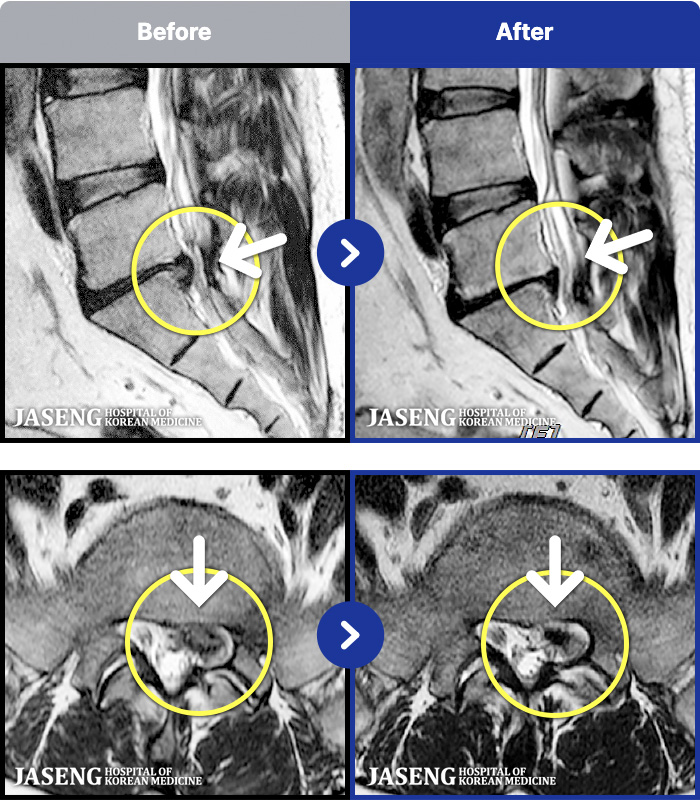

- MRI ġ

MRI ġ

1,301 MRI ũ ʸ Ȯϼ.